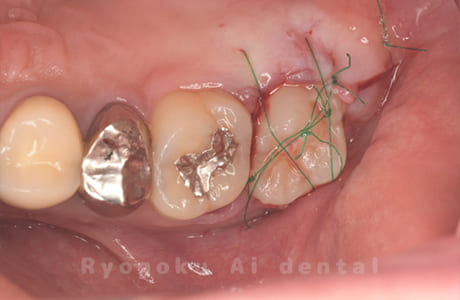

Case27

-

重度カリエス

歯牙移植咬合面術前 -

移植する親知らず

歯牙移植術直後咬合面

歯牙移植術後咬合面

歯牙移植術前側面

歯牙移植術中側面

歯牙移植術後側面

- 原因

- 重度カリエス

- 治療内容

- 自家歯牙移植、部分矯正

- 治療費用

- 220,000円(移植費用)

110,000円(部分矯正費用)

虫歯が大きく、保存不可能となった歯を上の親知らずと交換する自家歯牙移植を行いました。移植歯が小ぶりであったため、部分矯正を行い問題なく噛み合い、経過良好です。